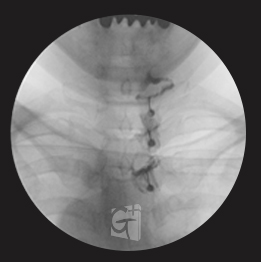

경추 신경성형술

경추 좌측 2번 신경절

경막외 카테터 삽입 -

척추관 안쪽으로 진입하여 약물 주입